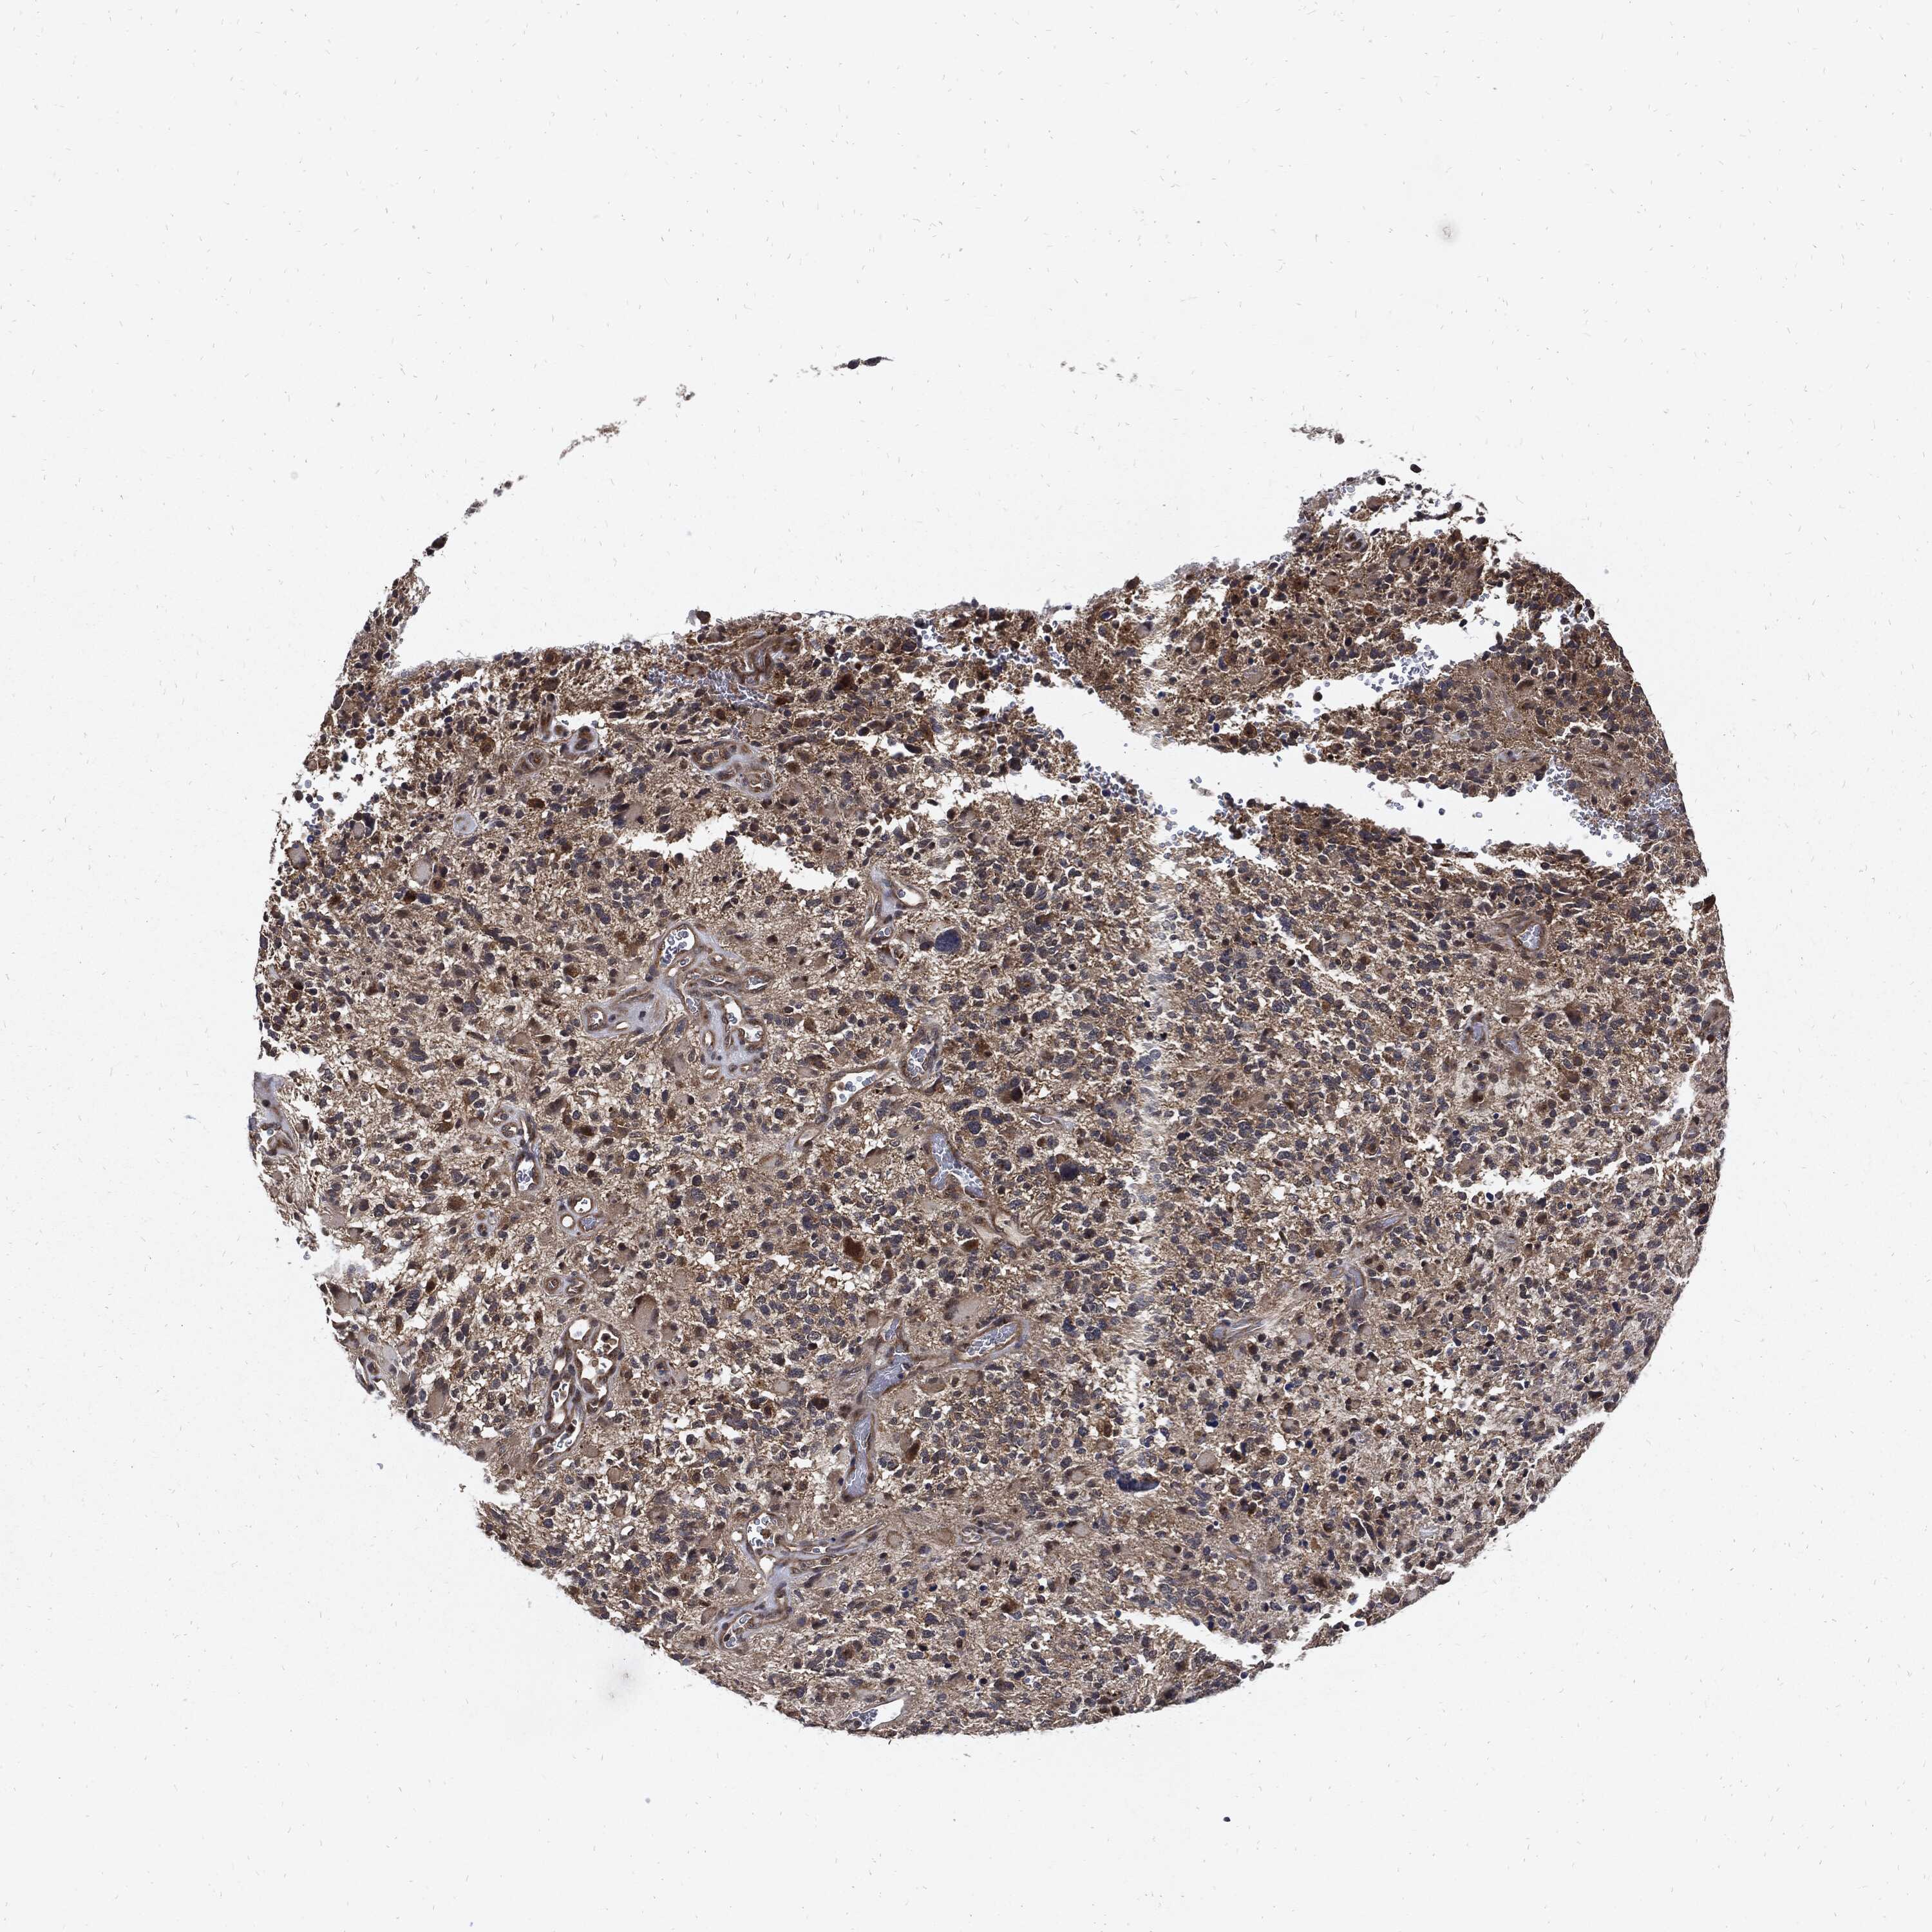

GLIOMA - Protein expressioni

A mouse-over function shows sample information and annotation data. Click on an image to view it in a full screen mode. Samples can be filtered based on level of antibody staining by selecting one or several of the following categories: high, medium, low and not detected. The assay and annotation is described here.

Note that samples used for immunohistochemistry by the Human Protein Atlas do not correspond to samples in the TCGA dataset.

Antibody stainingi

Antibody staining in the annotated cell types in the current human tissue is reported as not detected, low, medium, or high, based on conventional immunohistochemistry profiling in selected tissues. This score is based on the combination of the staining intensity and fraction of stained cells.

Each image is clickable and will lead to virtual microscopy that enables deeper exploration of all samples and also displays staining intensity scores, fraction scores and subcellular localization as well as patient and tissue information for each sample.

Antibody HPA034635

Antibody HPA069977

Antibody HPA071875

Antibody CAB009108

Staining

High

Medium

Low

Not detected

Intensity

Strong

Moderate

Weak

Negative

Quantity

>75%

75%-25%

<25%

None

Location

Nuclear

Cytoplasmic/membranous

Cytoplasmic/membranous,nuclear

Glioma, malignant, Low grade

Glioma, malignant, High grade